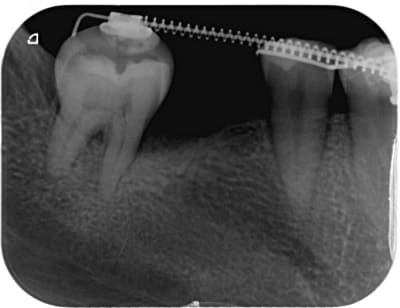

Et l'espace est suffisamment ouvert pour implanter. Je vous posterais les radios ce soir.

L'implant sera poser dans la semaine et je baguerait trois mois plus tard.

Non l'implant sera posé cette semaine puis temporisation de 3 mois .

L'on continuera à ouvrir l'espace en utilisant l'implant